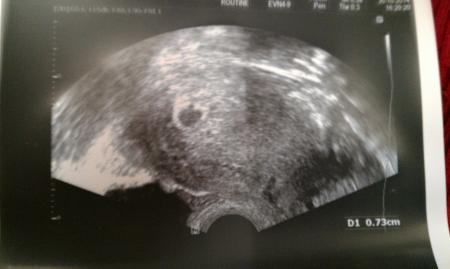

Es war gestern nur eine Fruchthöhle, Höhe 0,73 cm, zu sehen. Das Bild war leider auch etwas unscharf. Oh man, hoffentlich entwickelt die Blasenentzündung nicht weiter. Das macht mir etwas Angst.

Hier ist das Ultraschallbild von gestern

Da sehe ich aber einen schönen Dottersack, oder täusche ich mich?

In der Fruchthöhle leicht links oben ist ein heller kleiner Kreis zu sehen....meine ich zumindest. Auflösung ist nicht so schön. Aber wenn der Arzt nichts gesagt hat, dann bilde ich mir das wohl nur ein.

Vielleicht hast du recht. Du meinst unterhalb von dem Markierungspunkt der oberhalb der Fruchtblase ist, oder? Recht mittig. Ich seh da auch was, aber da muss man echt genau gucken ;)

Ja, genau. Aber es ist ja auch noch ganz früh. Wahrscheinlich wenn du morgen direkt wieder einen US machen lassen würdest, wäre er schon gut zu sehen. Das geht von jetzt auf gleich und dann schlägt auch schon das Herz